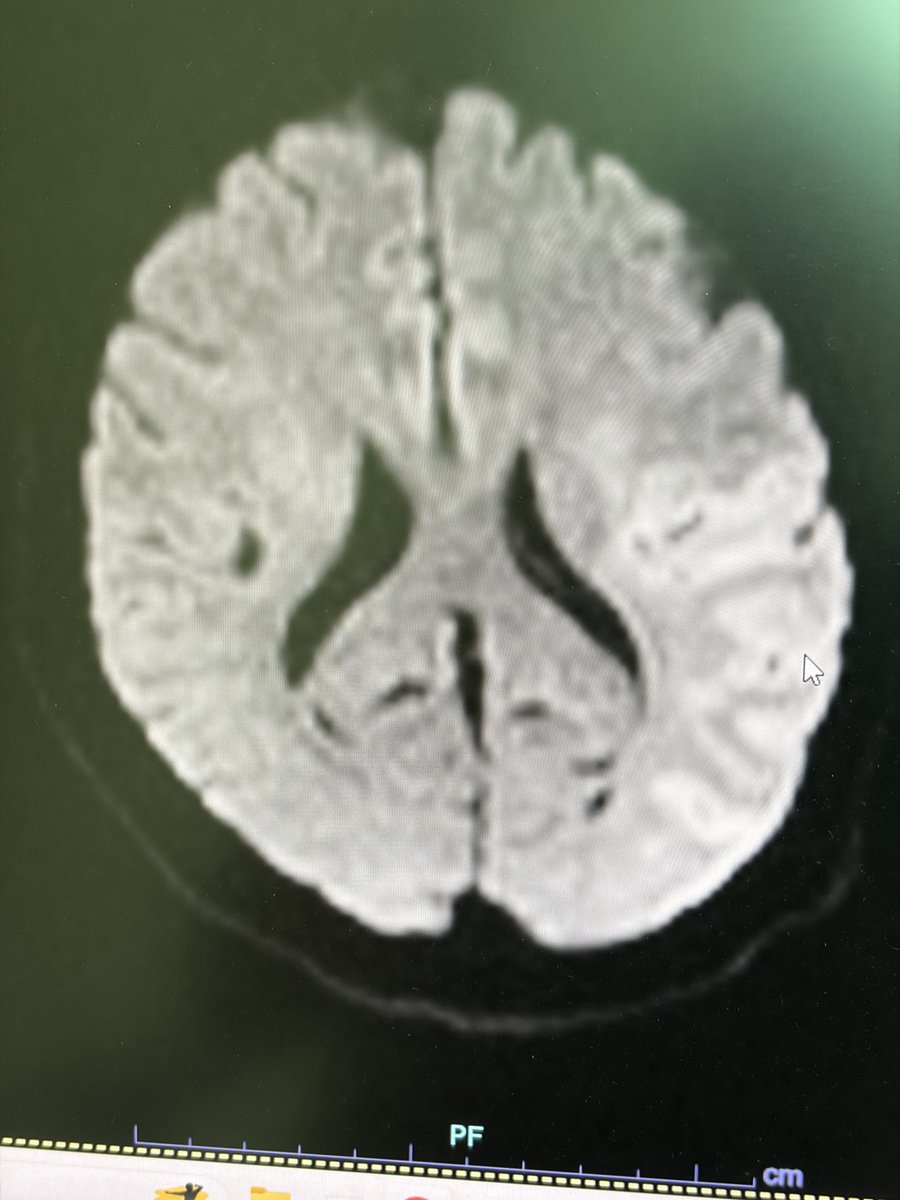

Two weeks ago, a 54-year-old patient recovering from open-heart surgery (CABG) suffered a major stroke. • Symptoms: Sudden inability to speak + right-side paralysis. • Action: Immediate Mechanical Thrombectomy to remove the brain clot.

Manish Kumar Yadav tweet mediaManish Kumar Yadav tweet mediaManish Kumar Yadav tweet mediaManish Kumar Yadav tweet media